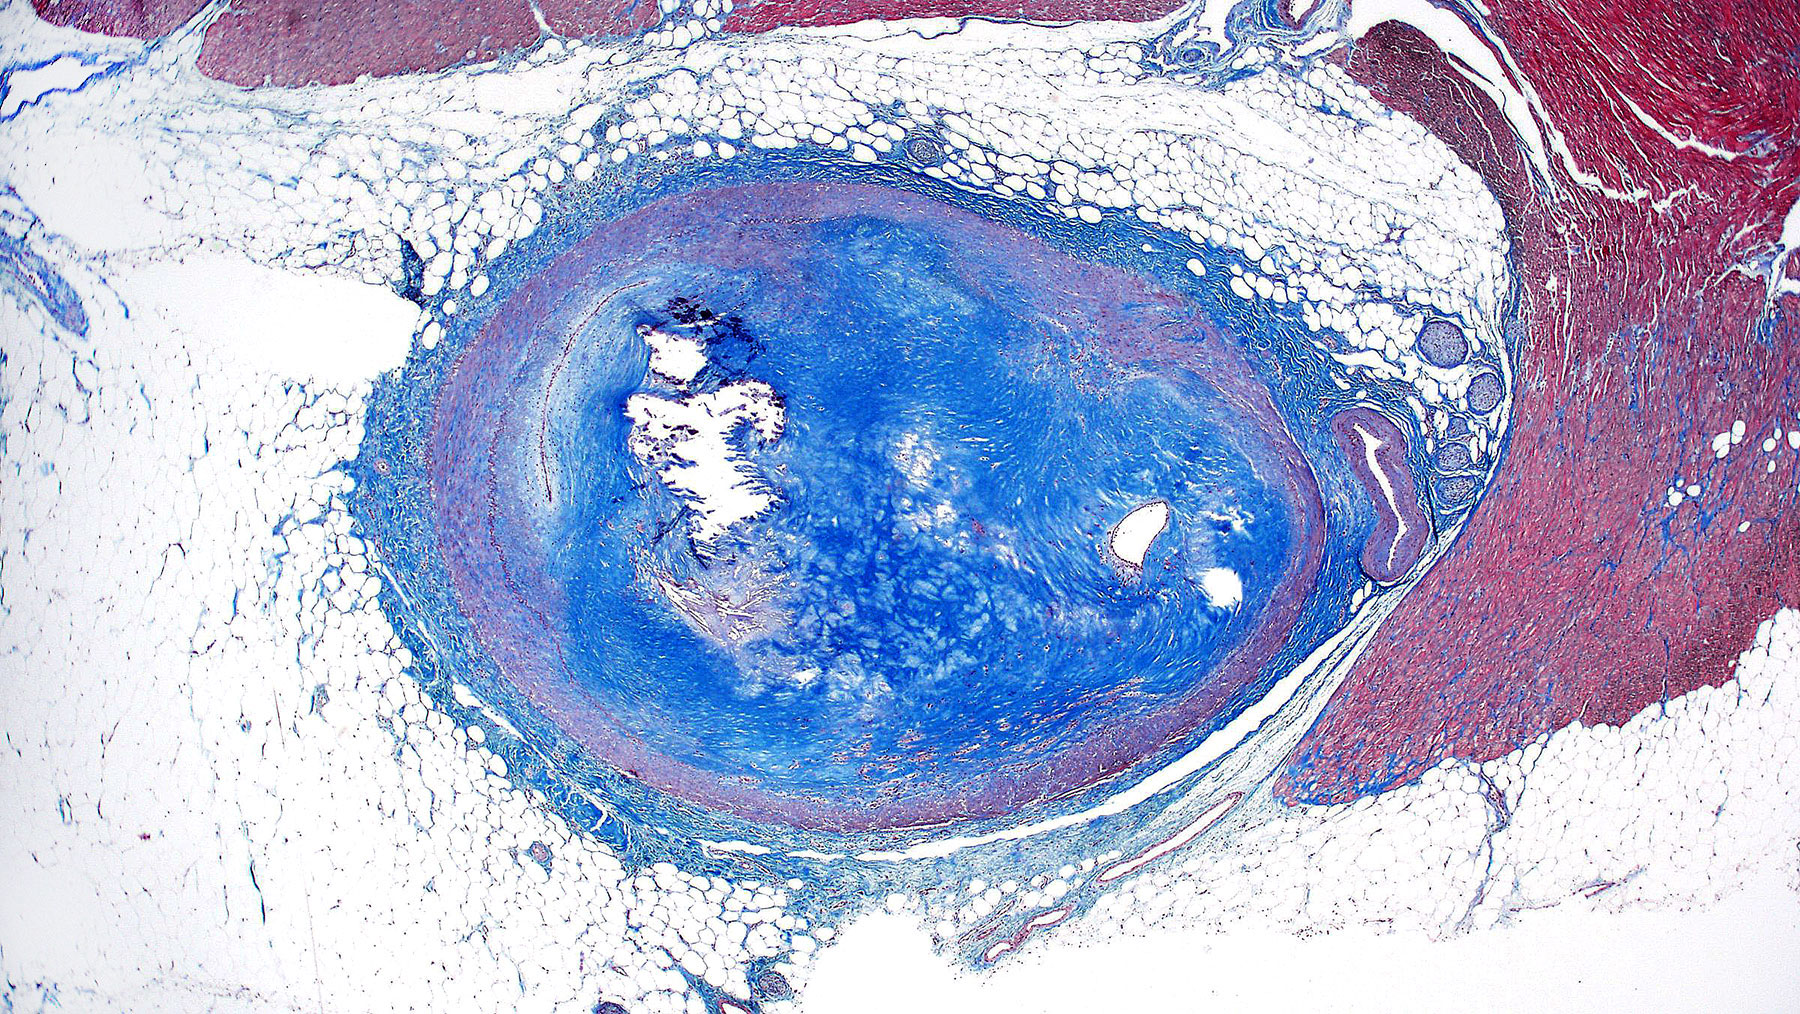

Figure B. Trichrome x2

Histology: Figure A shows coronary artery atherosclerosis with dystrophic calcifications on upper left hand side of the figure A (Calcifications appear bluish on H&S staining). There is >90% occlusion of the lumen (lumen shown by the arrow). Figure C shows the endothelial lining of the lumen. The fibrosis is confirmed by trichrome staining in Figures B and D.  All these finding are consistent with severe coronaryartery disease